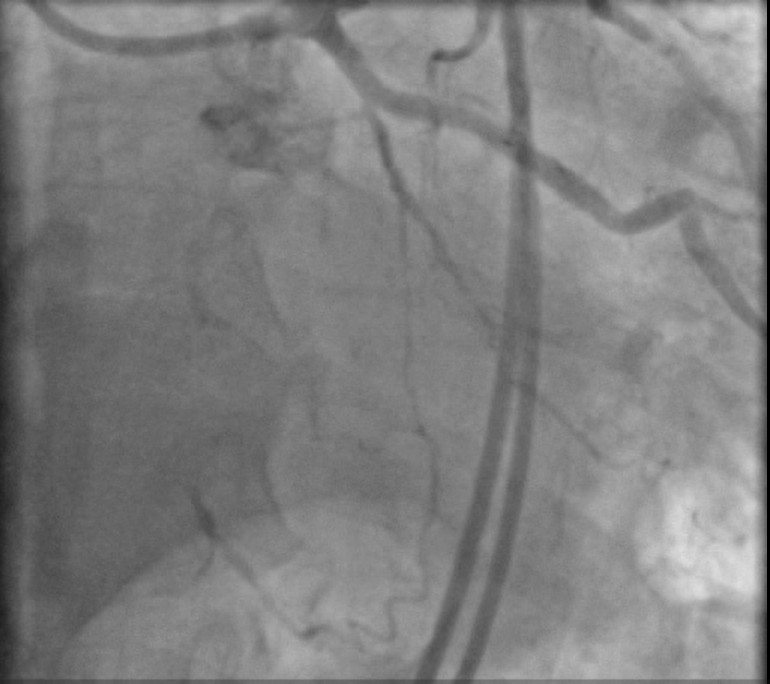

LM : Normal vessel bifurcating into LAD & LCX.LAD : Atherosclerotic vessel with patent previously deployed stent .LCX: A atherosclerotic small diffusely diseased vessel .RCA : Atherosclerotic vessel with proximal CTO with bridging collaterals and retrograde good septal and epicardial collaterals from left system

Dual femoral access , Dual injection through AL1 7F & XB4 7F Target vessel assessment ( RCA ) with calculation of J-CTO score then deciding which strategy we decided a Trial antegrade, If failed , Retrograde through septals , If failed , shift to epicardial collateral.Antegrade Trial with GAIA Wires , Corsair MC failed , Retrograde trial through septals failed as it seems not connected shifting strategy to epicardial : Sion blue navigated through epicardial collaterals , corsair 150 MC successfully passed through PL branch MC advanced to distal Cap & GAIA 2nd wire successfully pierced distal cap , but failed to entre antegrade guide Trial snaring through AL guiding by a home made snare but failed , Guiding changed to JR with successful snaring of wire into antegrade guide followed by MCPilot 50 wire introduced through retrograde MC ( Rendezvous Technique , Reverse TIP IN ) then MC Withdrawn we started conventional PCI with Antegrade Balloon dilatation 2.5 * 15 mm semicompliant then 3.5 * 15 mm NC balloons Then stenting with 2 overlapping DES with postdialtation with 4*15 NC balloon with final good angiographic results